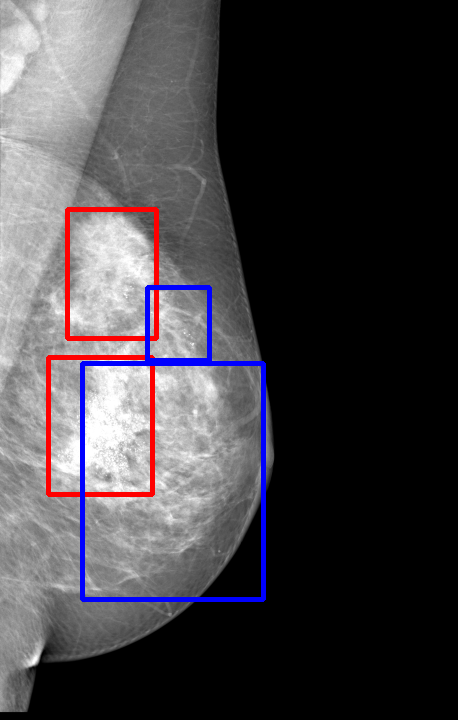

UDA has been extensively studied in case of natural images, utilizing techniques such as adversarial learning [21],pseudo-label training [6, 21, 40], image-to-image translation [40], graph reasoning [20], and adaptive mean Teacher training [6], improving domain adaptation efficiency of object detectors. Recently multiple works focused on using Mask autoencoders (MAE) methods in large-scale pretraining for vision models, involving masking parts of input and reconstructing them [12, 33]. However, these approaches overlook domain shifts. Alternatively, widespread utilization of Teacher-Student models, wherein a Teacher provides pseudo-labels for target domain (unlabeled images) to supervise a Student model, leads to notable adaptation improvements [40, 43]. However, these techniques face the challenge of incorrect predictions and excessive false positives per image due to low-quality pseudo-labels, particularly for medical imaging problems. Pseudo-labels are filtered from the Teacher model’s outputs based on the confidence score threshold. Selecting numerous pseudo-labels with low thresholds leads to inclusion of incorrect predictions, and compromising performance. Conversely, higher thresholds yield a limited number of pseudo-boxes, resulting in sub-optimal supervision. Existing Teacher-Student models often produce pseudo-labels riddled with errors and false positives, as illustrated in Fig. 1(a) and Fig. 1(b). Though [21, 40, 43] utilize techniques like adversarial alignment, weak-strong augmentation, and selective retraining of Student model to minimize the false positives in pseudo-labels, these approaches fail on medical images.

Contributions of this work. We note that screening mammography inherently differs from natural images, with breast abnormalities such as masses, asymmetries, and micro-calcifications, typically much smaller in comparison to the salient objects present in natural images, emphasizing the need for approaches specific to this problem. To address these issues, we make following contributions in this work: (1) We introduce D-MASTER, a transformer-based Domain-invariant Mask Annealed Student Teacher Autoencoder Framework for cross-domain breast cancer detection from mammograms (BCDM), integrating a novel mask-annealing technique and adaptive confidence refinement module. Unlike pretraining with mask autoencoders (MAEs) [12], leveraging massive datasets for training and then fine-tuning on smaller datasets, we present a novel learnable masking technique for the MAE branch that generates masks of different complexities, which are reconstructed by the DefDETR [44] encoder and decoder. Our approach, as a self-supervised task on target images, enables the encoder to acquire domain-invariant features and learn better target representations as shown in Fig. 1(c). (2) In Teacher-Student model, since the pseudo-label noise generated by the Teacher affects the Student model severely, we propose an adaptive confidence refinement module that progressively restricts the confidence metric for pseudo-label filtering. During the initial adaptation phase, soft confidence is applied allowing more pseudo-labels to learn better target representations. Subsequently, as confidence gradually increases, the focus shifts towards enhancing detection accuracy by prioritizing more reliable pseudo-labels. (3) We release a bounding box annotated subset of 1000 mammograms from the RSNA Breast Screening Dataset (referred to as RSNA-BSD1K) to support further research in BCDM. (4) We setup a new state-of-the-art (SOTA) in detection accuracy for UDA settings. We report a sensitivity of 0.74 on INBreast [25] and 0.51 on DDSM [18] at 0.3 FPI, compared to 0.61 and 0.44 using current SOTA respectively. Significant performance gains are also observed on our in-house and RSNA-BSD1K datasets.